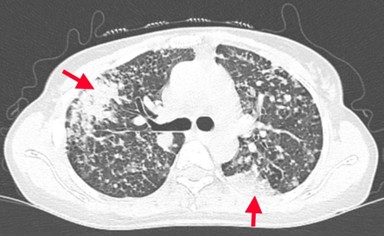

Bệnh nhân đi khám tại bệnh viện Bạch Mai được chụp cắt lớp vi tính lồng ngực phát hiện các đám tổn thương đông đặc phổi 2 bên, tổn thương đặc xương không đều các đốt sống D5, D8, D11 và xương sườn IV bên phải.

Hình 1: Hình ảnh tổn thương phổi trước điều trị: các đám tổn thương đông đặc, ranh giới không rõ, lan tỏa nhu mô phổi 2 bên.